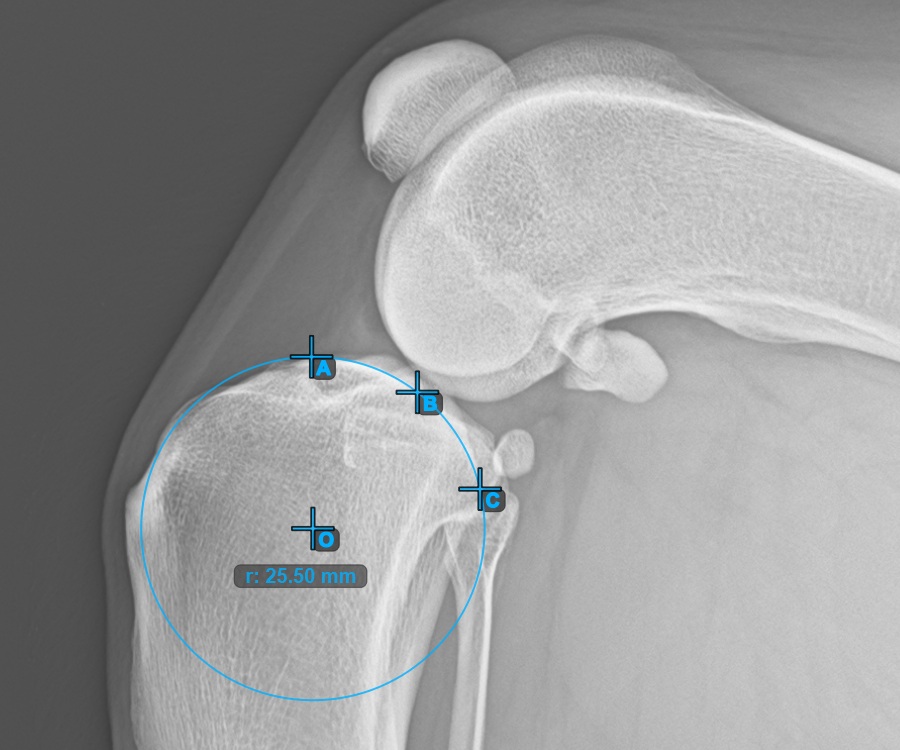

Continue by marking the three points on the articular surface of the Condylus Femoris.

Mark the three points on the main condylus of the femoral bone (Condylus Femoris). Regardless of the order, make sure to mark the most cranial point, the most caudal point and the midpoint of the Condylus Femoris. A circle will be automatically constructed based on the three placed points.

The image below represents a typical placement of the three points on the Condylus Femoris.